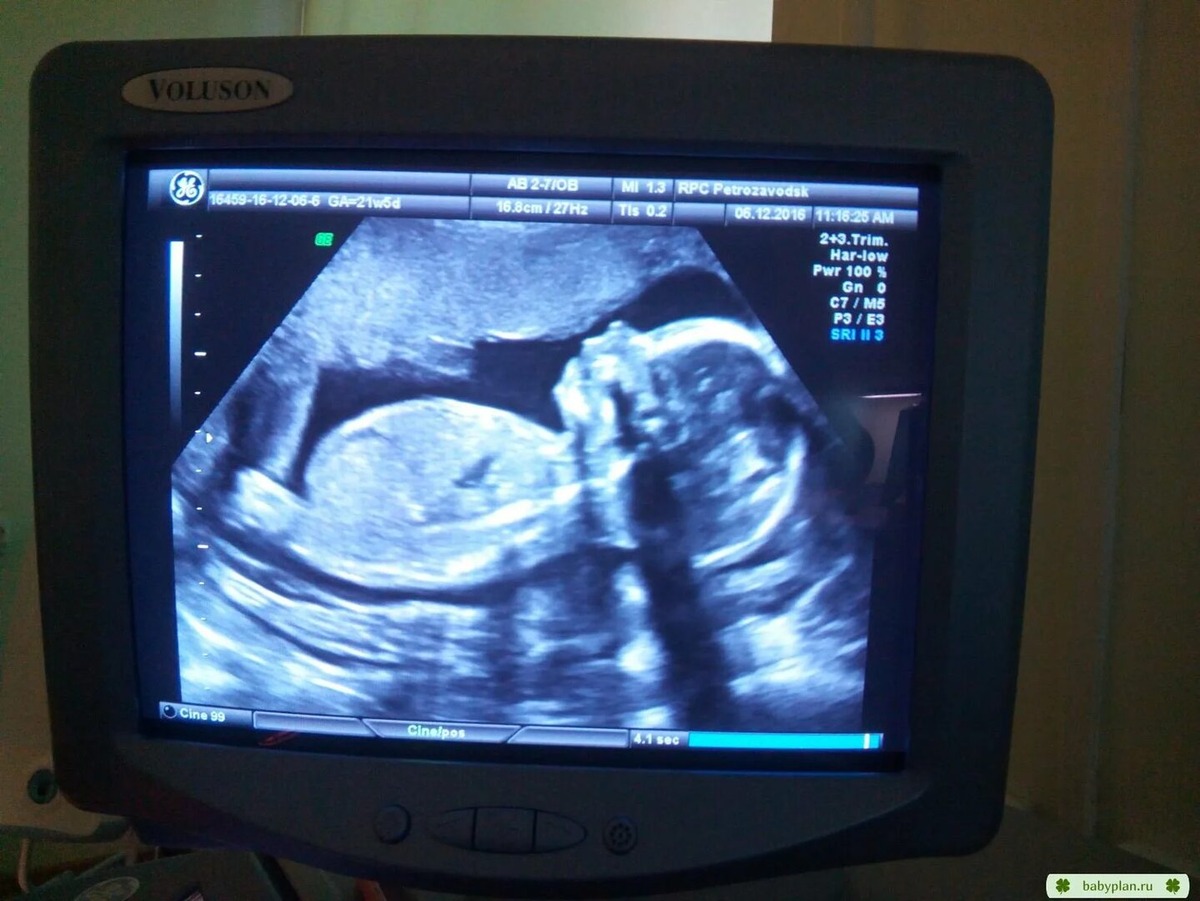

Вставлю картинку-скриншот.

Ну да ладно. Только разобрались более-менее с мононуклеозом, как подошло время первого скрининга. Я отпросилась сходить к моему врачу, отказавшись от бесплатного поликлинического УЗИ. Конечно же, притащила с собой и мужа. Он бессовестно отказался умилиться, пускать слезу, бурно радоваться... В общем вёл себя, как типичный дубовый чурбан, а не человек, впервые увидевший своего ребёнка воочию. Сказать, что я на него обиделась - это ничего не сказать. Потому от расстройства я, наверное, и была дальше невнимательна. Иначе бы забеспокоилась сразу.

- О, мальчик! - Радостно сказала врач. Я пропустила это мимо ушей, ну, какое определение пола на двенадцатой неделе? Потом шло долгое перечисление всего, из чего состоял мой ребёнок, включая число пальчиков. Дойдя до ног, она запнулась. Тогда я и это пропустила мимо ушей. Меня больше занимало, сделают ли фотографию. Плацента легла в устойчивое центральное предлежание. Опять где-то вылезла гематома... Ничего нового.

Из Яндекс картинок для иллюстрации

- Тебя не затруднит повторить УЗИ неделе так на пятнадцатой-шестнадцатой? - Спросила врач. Хочу ещё глянуть, а то до второго скрининга долго.

В указанный срок я снова отпросилась к ней на УЗИ.

- Ну, скажите, не видно ещё, кто там? - Спросила я, едва она взяла датчик в руку.

- На ЭТОМ аппарате, поверь мне, всё отлично видно. Ну, ладно, раз так хочешь, покажу ещё раз. - И она продемонстрировала мне то, что несомненно являлось частью тела мальчика, а не девочки.

- Что? Девочку хотела? - Улыбнулась она. - Ну, за девочкой в следующий раз придёшь. Теперь давай посмотрим то, что я хотела. - она повела датчиком немного в сторону. Поверила и так, и эдак, а потом, вздохнув, сказала:

- Да. К сожалению, мне не померещилось в прошлый раз. Но, если хочешь, давай я тебе дам направление к нам в перинатальный. Пусть тебя посмотрит ещё доктор С. Она у нас лучшая по УЗИ диагностике аномалий развития.

- Ноги. Вот, смотри, - она развернула монитор поудобнее, - Видишь, как ступни завёрнуты?

Я видела. Одна ступня была согнута в голеностопе почти на сто восемьдесят градусов и лежала практически параллельно голени. Второй ногой он дрыгал, но ступня тоже казалась в форме кочерги.

- Это врождённая косолапость, - продолжала врач. - Чаще всего она не сопровождается больше никакими патологиями. Дети умственно абсолютно полноценны. Погоди, я ещё раз внимательно посмотрю ручки на всякий случай...